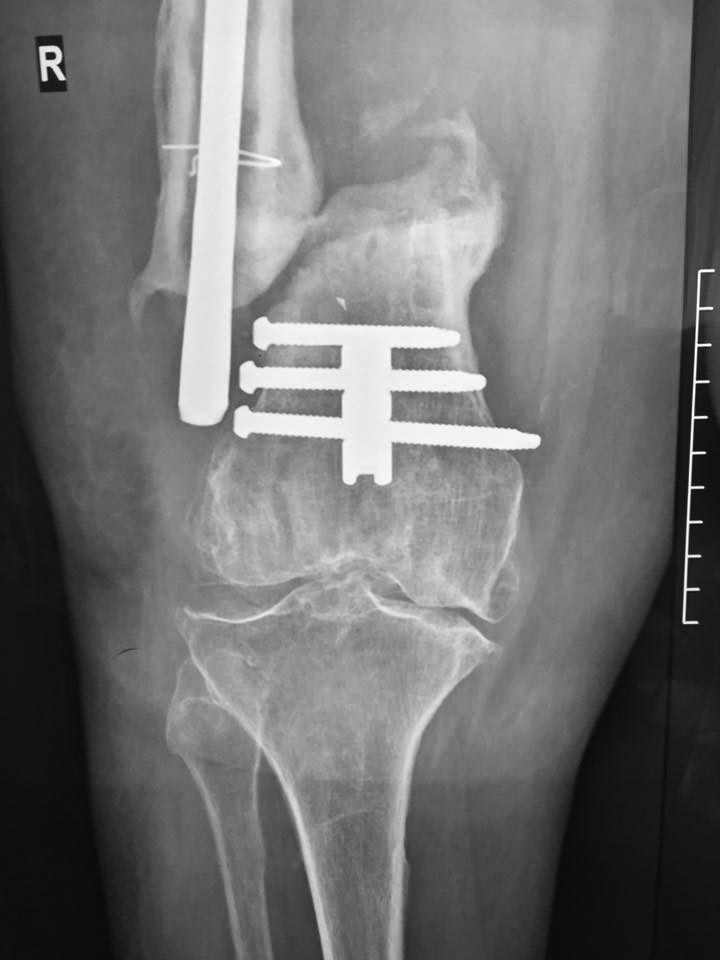

Пациентка 72 года поступила в клинику с диагнозом несросшийся в условиях остеосинтеза перелом н/3 правой бедренной кости, перелом фиксатора ( в анамнезе 3 неудачные операции на бедре по поводу вышеуказанного диагноза). Интересует Ваше мнение по поводу тактики лечения пациентки.